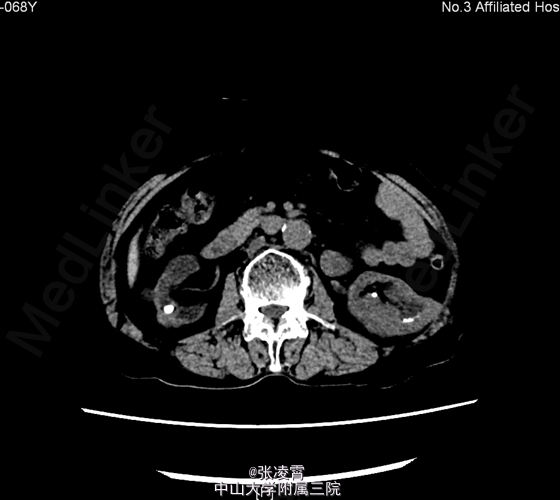

患者,女性,68岁,因“双侧腰部疼痛1周“入院。患者1周前无明显诱因下出现双侧腰部隐痛,可忍受,每次持续1小时,有尿频、尿急、间接性尿痛,有夜尿,每夜可达4次。 既往史:2010年及2012年于我院泌尿外科二区行经皮肾镜碎石术

当地医院B超提示:肾功能受损改变,右肾多发结石。 CTU:1、双肾多发结石,双肾轻~中度积液、炎症;双肾萎缩,双肾功能减低2、双肾多发囊肿3、腹主动脉、双侧髂动脉硬化 核素肾动静态显像:1、右肾灌注、功能中度受损,右上尿路不完全性梗阻可能性大。2、左肾灌注、功能中度受损。 肌酐:281.000umol/L 尿素氮:14.220mmol/L 尿常规:白细胞计数 28.1个/ul

诊断:1.双肾结石 ;2.泌尿道感染;3.肾功能不全 经完善相关术前检查,予行双侧输尿管软镜下碎石术。手术耗时约3小时,手术顺利,出血约5ml。